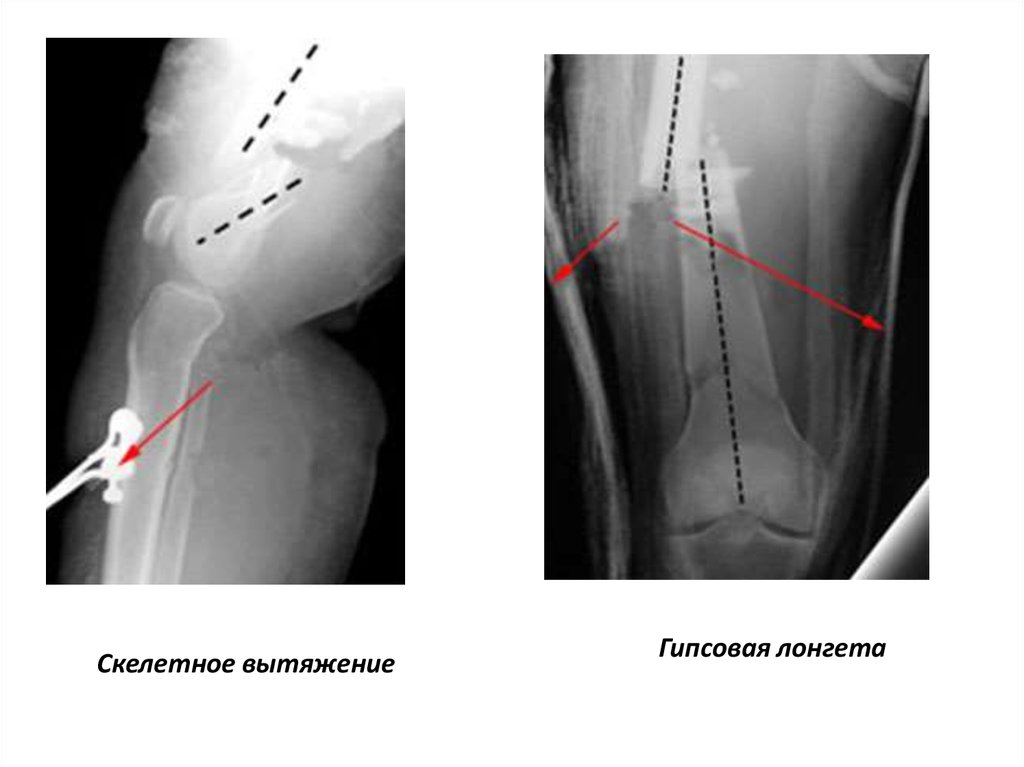

На рентгенограмме

коленного сустава в

боковой проекции

видно укорочение

мышц передней и

задней группы

бедра,что

сопровождается

смещением костных

фрагментов

Скелетное вытяжение

Гипсовая лонгета